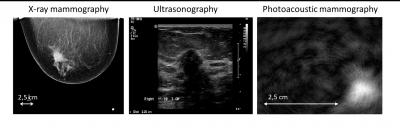

By comparing the photoacoustic data with conventional diagnostic X-rays, ultrasound imaging, MRI, and tissue exams, the researchers showed that malignancies produced a distinct photoacoustic signal that is potentially clinically useful for making a diagnosis of breast cancer. The team also observed that the photoacoustic contrast of the malignant tissue is higher than the contrast provided by the conventional X-ray mammographies.